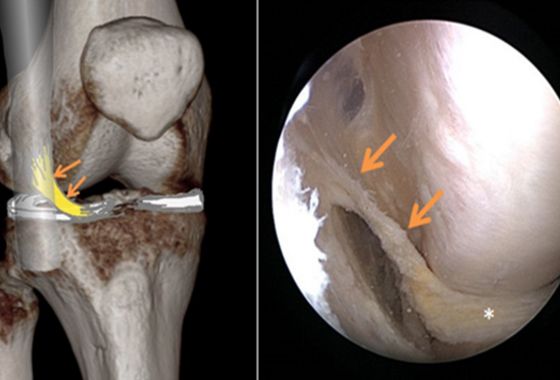

Das Kniegelenk wird sehr häufig mittels MRI untersucht und auch während Operationen regelmässig auf Abnormitäten geprüft. Man meinte bisher, die Anatomie dieses Gelenkes bis ins Detail zu kennen. Das AIML aber war bis heute noch nicht beschrieben worden. Es ist ein schmaler Faserzug, der zwischen dem Tractus iliotibialis (einem Sehnenstrang entlang der Aussenseite des Knies) und dem Aussenmeniskus verläuft.

Das AIML ist laut der soeben veröffentlichten Studie eine anatomische Variante der Aufhängung des Aussenmeniskus. In einer Analyse von MRI-Untersuchungen bei über 1000 Personen war das AIML in 13% der Fälle vorhanden. Die Studie wurde von Forschenden der Orthopädie und Radiologie der Universitätsklinik Balgrist durchgeführt.

Obwohl es sich um eine anatomische Variante handelt, ist das Vorhandensein eines AIML im Kniegelenk klinisch bedeutsam. Menschen mit AIML haben ein deutlich erhöhtes Risiko für Risse des Aussenmeniskus als der Rest der Bevölkerung.